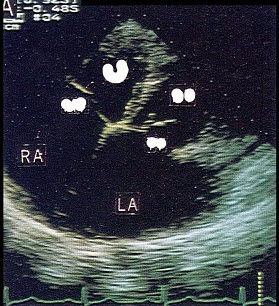

42、单项选择题

该图表明()

A.房室连接一致

B.房室连接不一致

C.大动脉转位

D.房室不定位

E.以上都不是